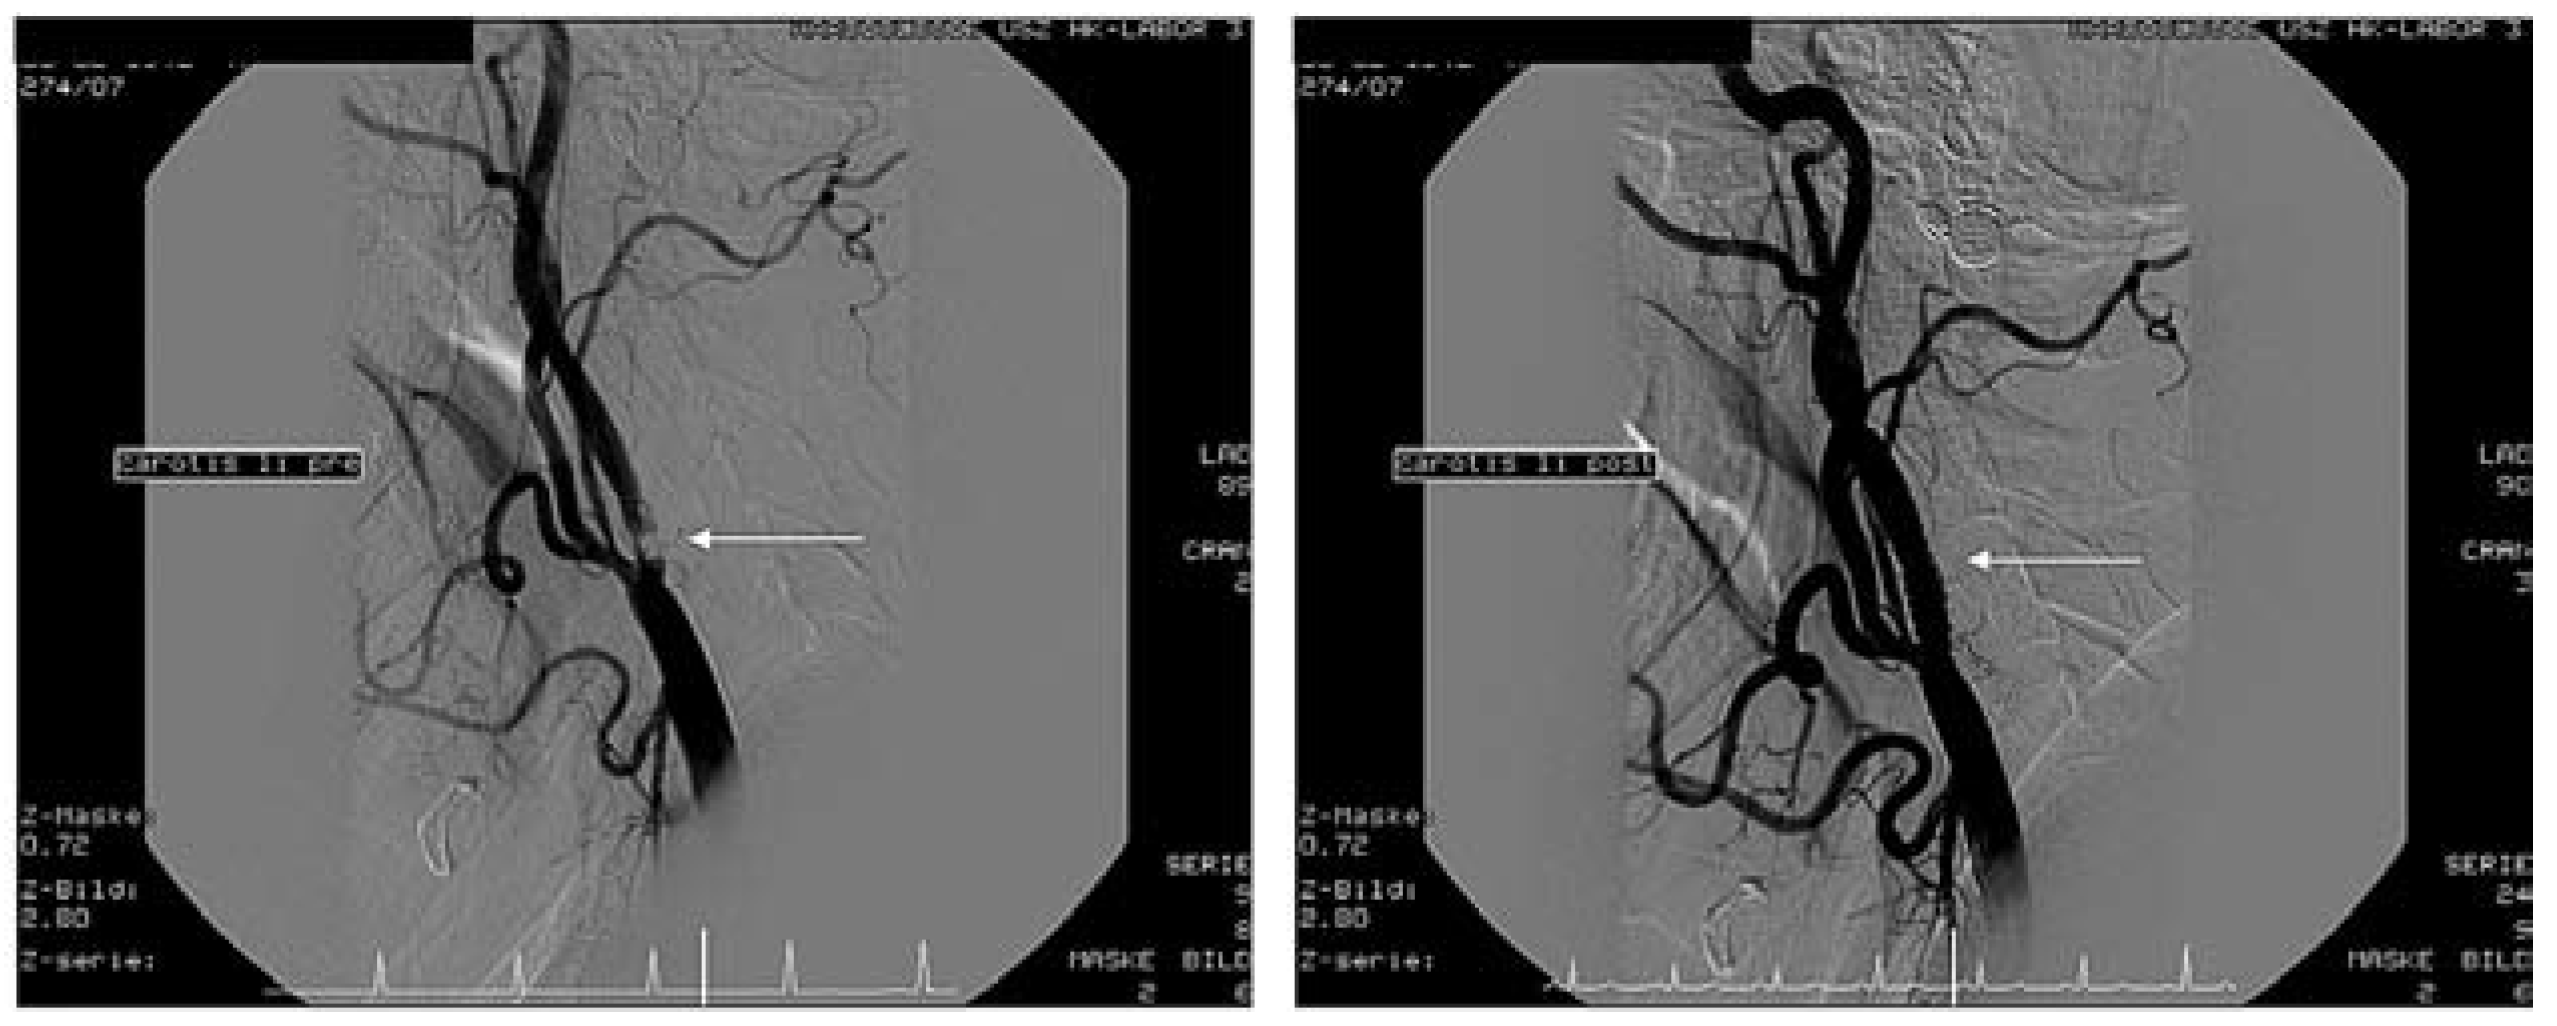

Schliesslich entwickelte sich das Karotis-Stenting zu einem bedeutenden Eingriff für interventionelle Kardiologen. Neue Technologien besonders durch Verwendung von so genannten Filter-Devices zur Vermeidung von zerebrovaskulären Embolien aus rupturierten Plaques haben die Ergebnisse erheblich verbessert. Am UniversitätsSpital Zürich wurden in den letzten Jahren über 140 solche Eingriffe mit einer minimalen Komplikationsrate (30-Tage-Mortalität-, Herzinfarkt- und Schlaganfall-Risiko 2,1%) auch bei Hochrisikopatienten durchgeführt (

Figure 3 and

Figure 4). Diese Ergebnisse machen deutlich, dass sich das Karotis-Stenting heute zu einer Alternative der Karotis-Endarterektomie entwickelt hat.